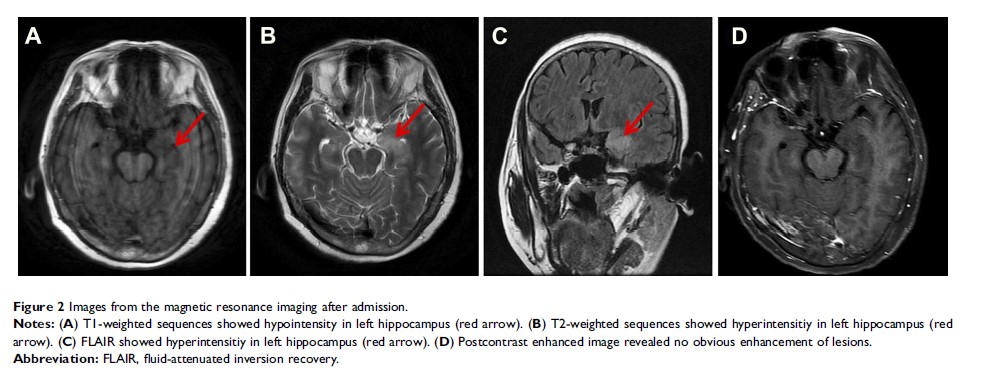

在小细胞肺癌中抗 SOX1 和抗-GABAB 受体抗体与自身免疫性脑炎共存:一个病例报告